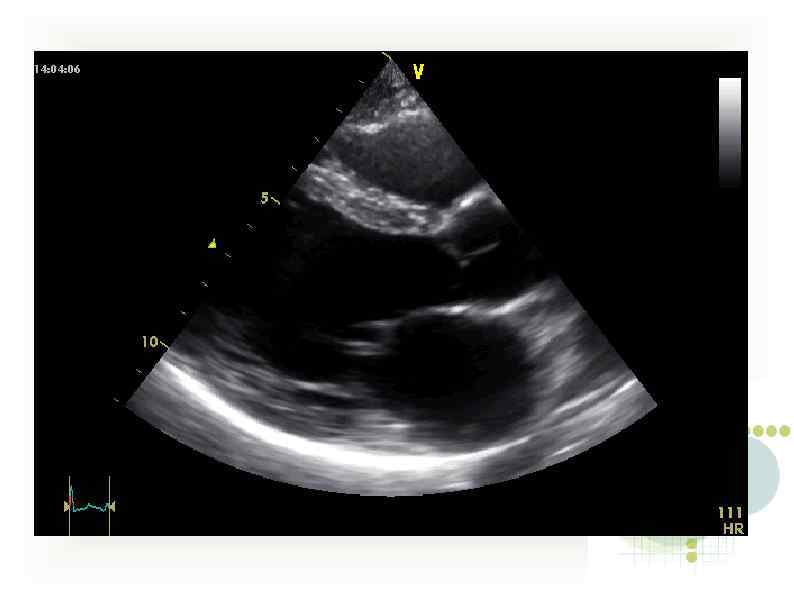

Эхо-кг 2/10/11 При сравнении с предыдущим исследованием отмечается заметная положительная динамика в виде уменьшения Эхо-кг 2/10/11 При сравнении с предыдущим исследованием отмечается заметная положительная динамика в виде уменьшения размеров левого желудочка и улучшения сократительной функции